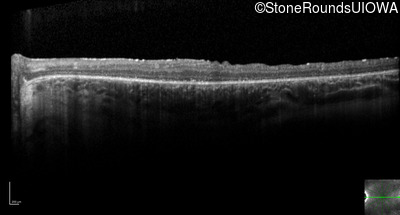

Optical Coherence Tomography - Left - 20/50

Exemplar / OCT Stack

OCT Stack